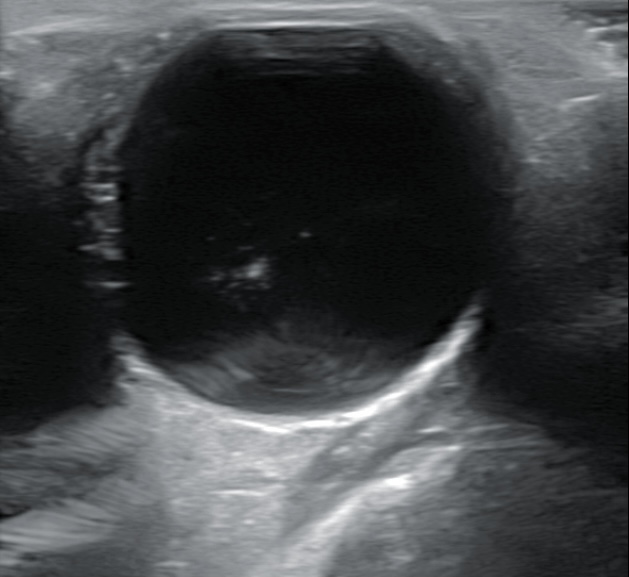

Hallazgos ecográficos

Se realiza ecografía donde se aprecia DVP en ojo derecho sin descartar hemovitreo y en campo superior y nasal una membrana más gruesa.